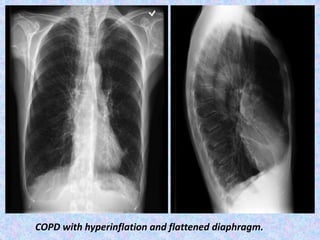

COPD with hyperinflation and flattened diaphragm.

COPD with hyperinflation and flattened diaphragm and widening of retro-sternal space

COPD with hyperinflationand flattened diaphragm.

COPD with hyperinflationand flattened diaphragm and widening of retro-sternal space

Abnormal chest X-ray findings are usually not seen until COPD is

severe. In this case, the X-ray may show:

Flattening of the diaphragm, the large muscle that separates the lungs and heart

from the abdominal cavity.

Increased size of the chest, as measured from front to back.

A long narrow heart.

Abnormal air collections within the lung (focal bullae).

On the lateral radiograph, a "barrel chest" with widened anterior-posterior

diameter may be visualized. The "saber-sheath trachea" sign refers to marked

coronal narrowing of the intrathoracic trachea (frontal view) with concomitant

sagittal widening (lateral view).